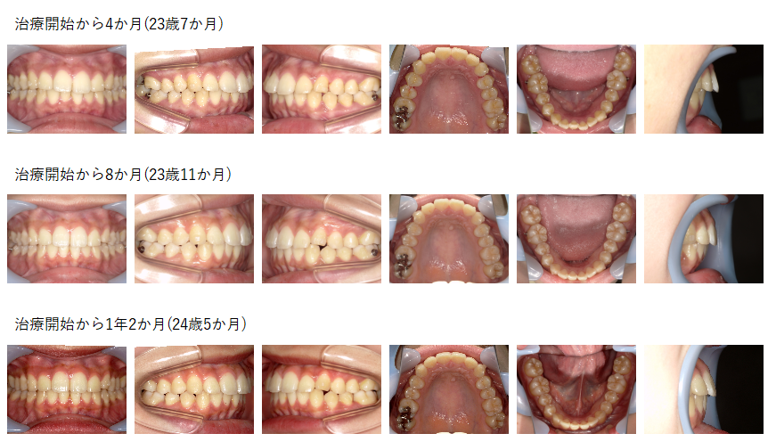

【治療例 K5098】初診時年齢:23歳3か月 / 性別:女性 / 主訴:出っ歯になってきている気がする

幼少期に当院にてサービカルヘッドギアとマルチブラケット装置を使用して治療したが、成人になってから出っ歯を主訴に来院された。IPRを行いながら、上顎前突と正中の不一致の改善をインビザライン®にて再治療した症例である。

主訴:出っ歯になってきている気がする

診断名:下顎歯列正中が左方偏移した上顎前突症例

使用した主な装置:アライナー型(マウスピース型)矯正装置(インビザライン®)、顎間ゴム

抜歯/非抜歯および抜歯部位:非抜歯

※こちらの症例は2023年12月から2025年7月に行った矯正治療です(現在も経過観察中)

治療期間:1年7か月

治療回数:14回

アライナー枚数:初回22枚+追加①17枚 合計39枚使用